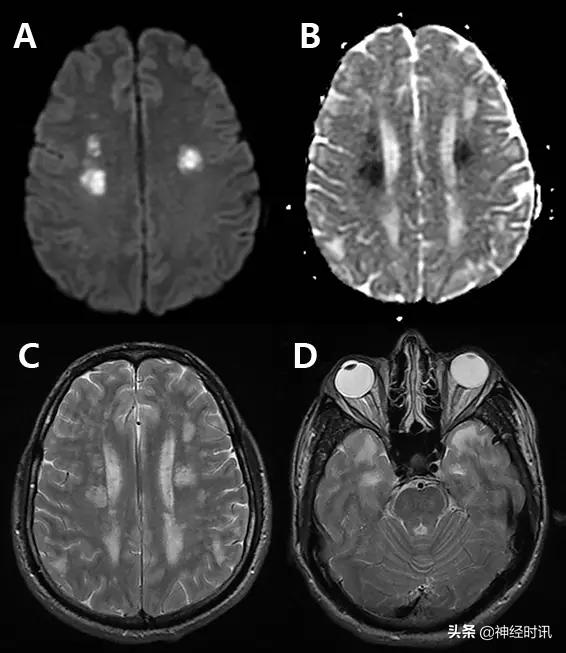

三分之一的卒中类似疾病是由于癫痫发作或发作后功能障碍导致。有时癫痫也可导致弥散受限(图2)。其分布特点不符合血管分布,水肿和脑回增强出现更早,脑灌注正常或增加,无血管闭塞,有时同时有皮层弥散受限和皮层下弥散增加。

图2 一例66岁男性,癫痫发作伴意识状态改变、急性失语和右侧凝视,拟诊脑卒中并给予IV-tPA治疗。左侧病灶情况下的右侧凝视可提示癫痫发作。他的入院MRI显示左侧额顶叶皮层和皮层下白质弥散受限(A和B)和水肿(C)。他的症状和影像学(图像未提供)显示在出院前完全缓解。